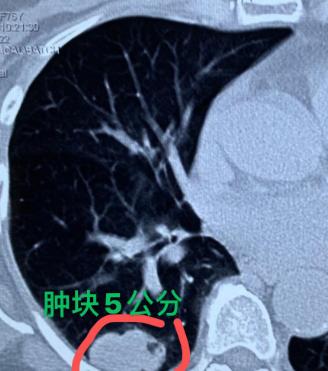

最近接诊的一个案例,让我心里特别不是滋味,想拿出来跟大家好好说说,希望能给更多人提个醒!患者是位76岁的老太太,10个月前体检的时候,查出右下肺有个1厘米的实性结节。 当地的医生就明确建议她尽快手术切除,可老太太一是害怕手术,二是平时没觉得有任何不舒服,就没把这个建议放在心上,总觉得“应该没什么大事”。 就这么拖着,一晃10个月过去了。直到最近,老太太开始频繁觉得胸闷,在儿女的反复劝说下,才不情不愿地来医院复查。一看到她的检查结果,我心里就咯噔一下,之前1厘米的小结节,已经长成了5厘米的大病灶。 不敢耽搁,立马安排老太太做了全身检查,万幸当时的结果显示没有出现远处转移。和家属、患者反复沟通商议后,我们确定了手术切除的治疗方案,本想着能通过手术彻底解决问题,可手术中出现的情况,还是超出了我们的预期。 打开胸腔后,我们发现她的胸膜和膈肌上,长了不少密密麻麻的小白点。凭着多年的临床经验,我瞬间就意识到,这是肿瘤长大之后,突破了胸膜,导致癌细胞在胸膜腔里播散转移了。当场做了活检冰冻病理,结果也证实了这个判断。 事已至此,我们还是按原计划切除了病变的肺叶,同时做了淋巴结清扫。现在只能寄希望于术后能找到合适的靶向药或者免疫药,通过后续的药物治疗帮她延长生命。 说真的,每次遇到这种因为拖延耽误治疗的案例,我都特别痛心。这里必须严肃提醒大家,查出肺实性结节,千万不能掉以轻心。 哪怕医生初步判断可能是炎症,也得按要求吃完消炎药,短期内及时复查确认情况。别总觉得自己身体没不舒服就没事,很多肺部病变初期都是悄无声息的,定期复查、遵医嘱治疗,才是对自己生命负责。[作揖][玫瑰]